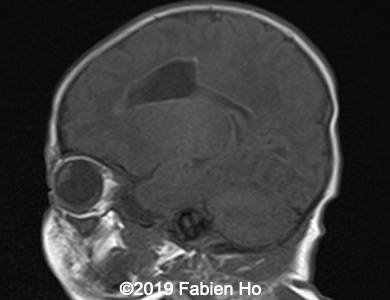

Images 1-3: in the left frontal lobe, hyperechoic with hypoechoic center lesion within the deep and periventricular white matter. Interestingly, this lesion has no mass effect on the lateral ventricle, and it has smooth margins.

Images 4-11, fetal brain MRI at 28 weeks: the left frontal lesion hence shows DWI hyperintensity, with T2* and T1 peripheral hyperintensity: ischemia with peripheral subacute hemorrhage. Note also that there is an associated blood clot in the left lateral ventricle. There is no obvious mass effect, nor peripheral edema. All these findin>gs are very suggestive of a clastic lesion.